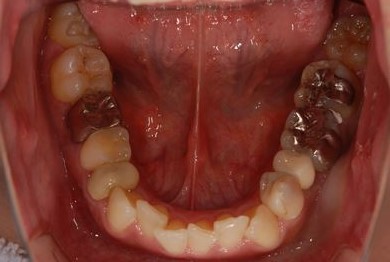

| 性別/年齢 | 女性 / 29歳 | ||||||||||||||||||||||||||||||||

| 主訴 | 以前治療中のままだった部位の歯の根に膿が溜まって、痛みと腫れが出た。応急処置で切開して膿は取ってもらったが、根の治療がまだなので、お願いしたい。 | ||||||||||||||||||||||||||||||||

| 治療方針 | 抜歯と同時にインプラント埋入を行い、治療期間を短縮する。 | ||||||||||||||||||||||||||||||||

| 治療内容 | インプラント2本(抜歯即日スピードインプラント)、ハイブリッドセラミッククラウン3本 | ||||||||||||||||||||||||||||||||